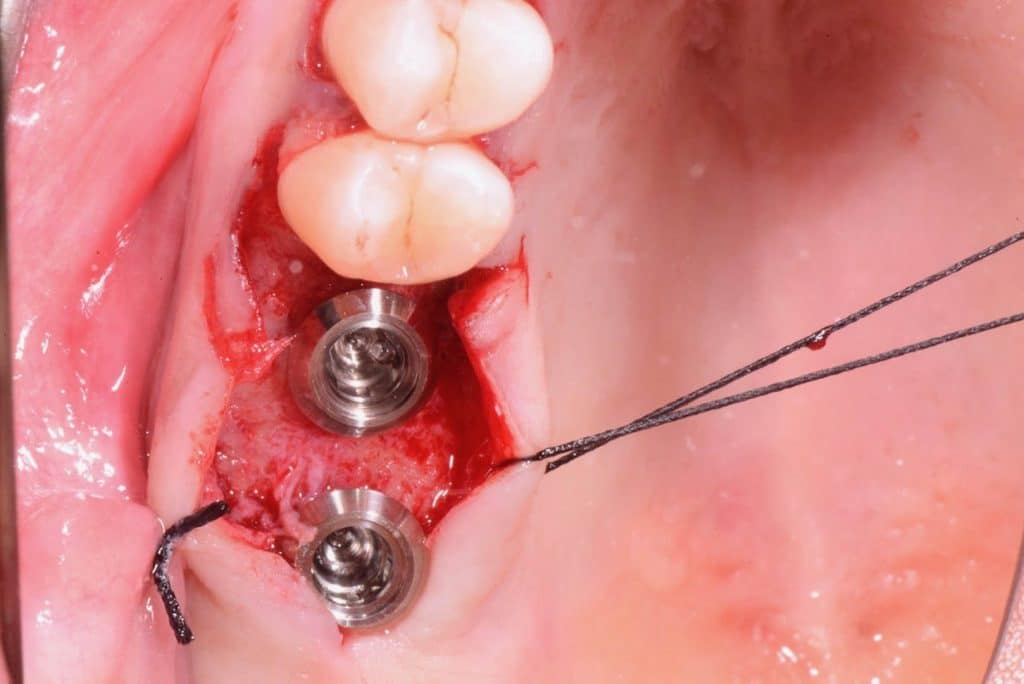

Two 8mm Straumann Wide-Neck have been inserted. After inserting a healing abutment with a height of 2 mm, a detached stitches suture was made. Good planning allowed me to be precise with the incision, and only 2 stitches have been necessary.